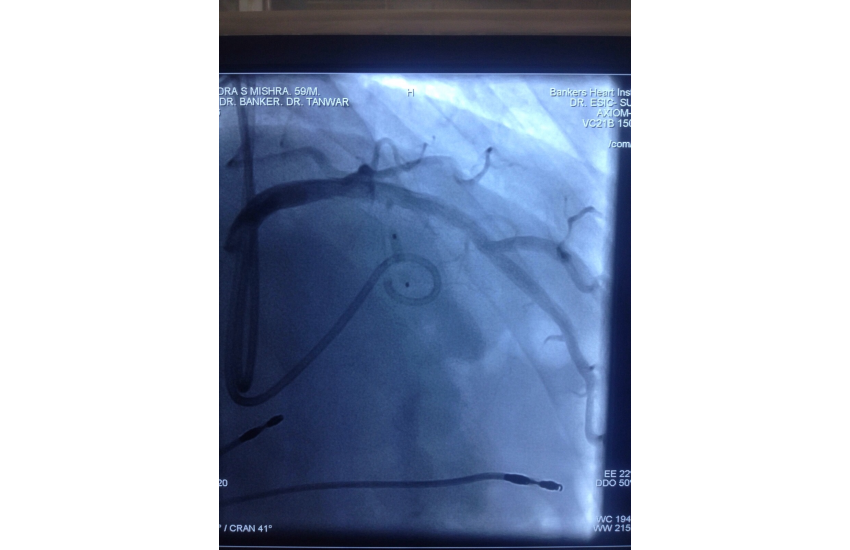

75 years old male presented with unstable angina undergone CAG which is shown LMCA bifurcation lesio